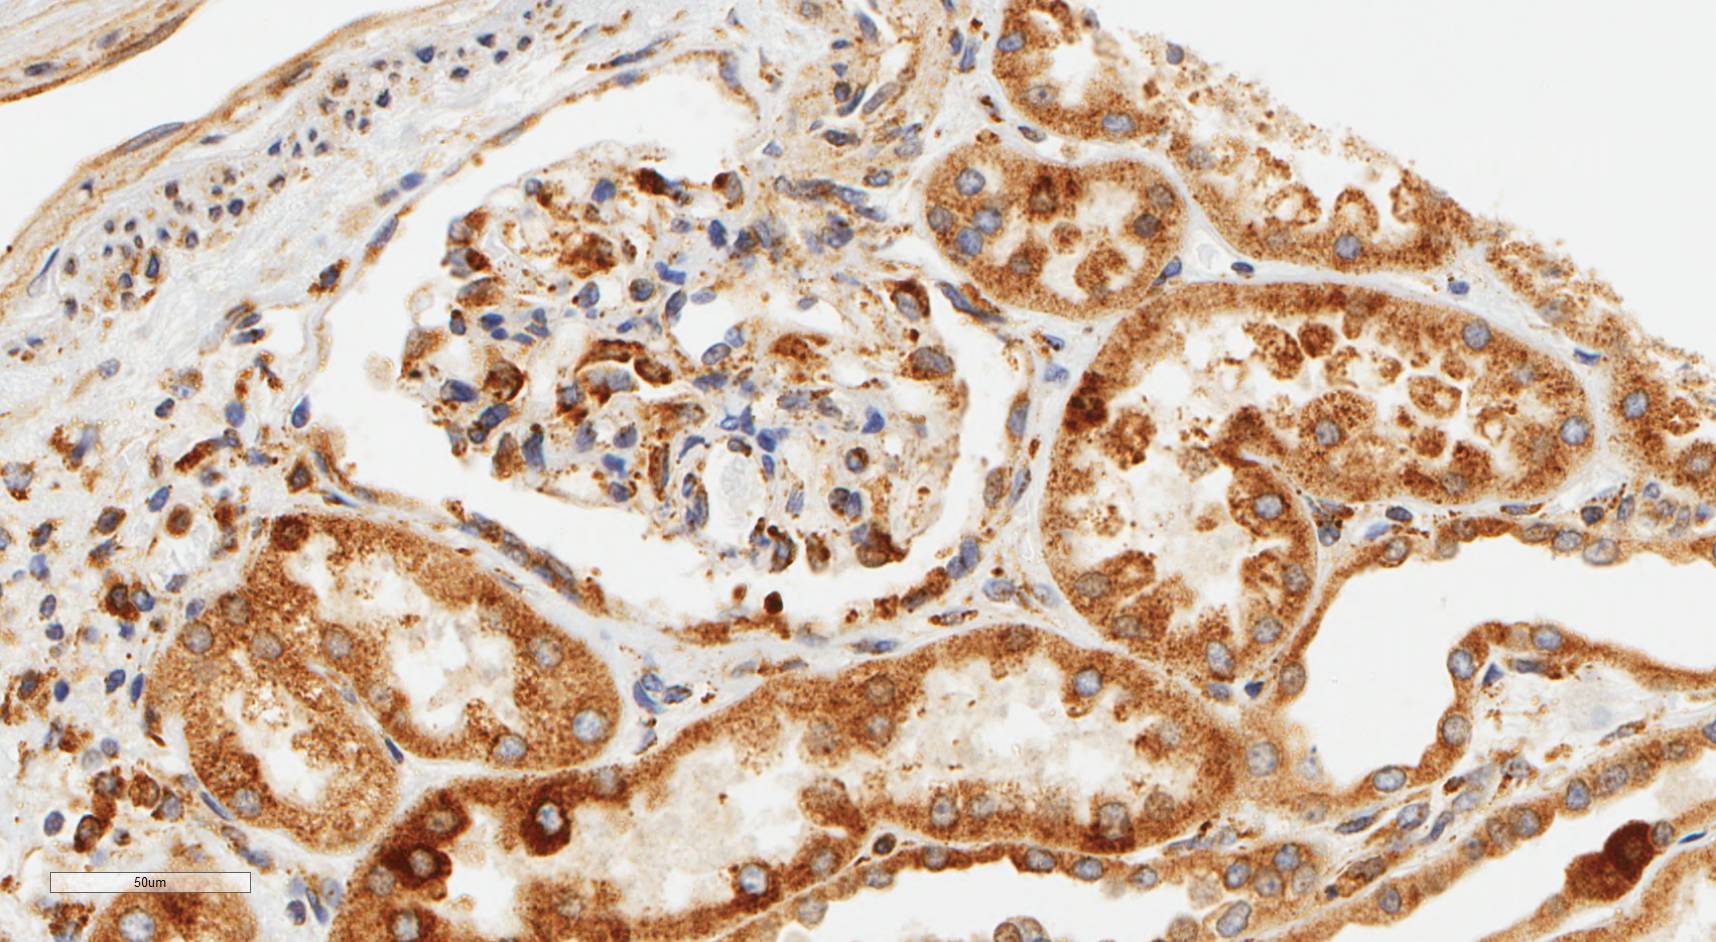

Laminin N terminus alpha31 (LaNt a31) is a really interesting laminin-related protein that the Hamill lab has been investigating for a while. Until recently, our studies focused entirely on the epithelial tissues of the skin, the surface of the eye and oral squamous cell carcinoma. However, we’ve always known that this relatively unstudied protein is also expressed by other tissues. As a first (and really important) step to understanding what this protein’s role is in tissue function, we used our new mouse monoclonal antibodies against the human form of LaNt a31 to screen a wide-range of human tissues.

Below you can see some of our favourite images from the selection. Click on an image to view as a slideshow.

You can see the whole story in the paper by Lee Troughton et al., available here.